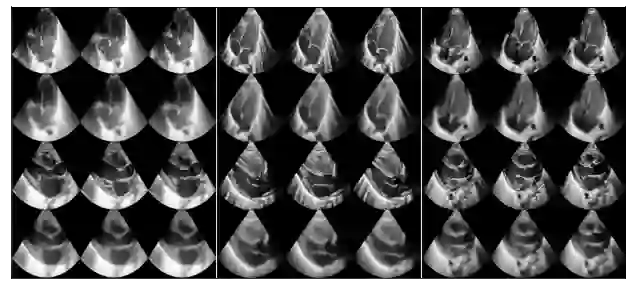

We propose a novel anomaly detection method for echocardiogram videos. The introduced method takes advantage of the periodic nature of the heart cycle to learn different variants of a variational latent trajectory model (TVAE). The models are trained on the healthy samples of an in-house dataset of infant echocardiogram videos consisting of multiple chamber views to learn a normative prior of the healthy population. During inference, maximum a posteriori (MAP) based anomaly detection is performed to detect out-of-distribution samples in our dataset. The proposed method reliably identifies severe congenital heart defects, such as Ebstein's Anomaly or Shonecomplex. Moreover, it achieves superior performance over MAP-based anomaly detection with standard variational autoencoders on the task of detecting pulmonary hypertension and right ventricular dilation. Finally, we demonstrate that the proposed method provides interpretable explanations of its output through heatmaps which highlight the regions corresponding to anomalous heart structures.